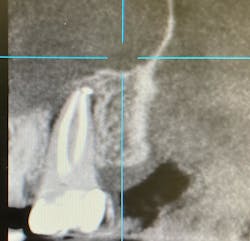

No. 3: Evaluate the radiographs.

Check the radiograph for a lateral defect (lucency) in the bone with little or no apical disease (figure 1). Cases where the disease shows bone loss lateral to the root, but the previous root canal treatment looks to have been filled to the apex, are likely fractures.

No. 4: Evaluate a cone beam CT scan.

If you can use a CBCT scan, it will give you more detail and can be helpful in discerning the pattern of bone loss, although it won’t necessarily show the root fracture itself. Failure of endodontic treatment commonly occurs at the portal of exit apically (unless there is a lateral canal midroot). Fractures are typically present with lateral bone loss (figure 2).